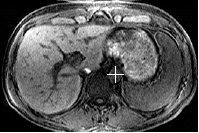

Figure 3. Tracker Position on Axial Abdomen